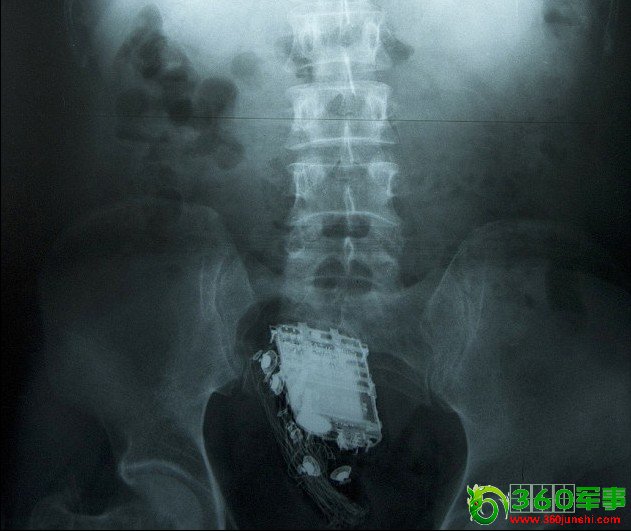

男子为躲避检查 将手机塞进肛门(图)

斯里兰卡一名囚犯为了躲避检查,竟然将手机藏进屁股里。